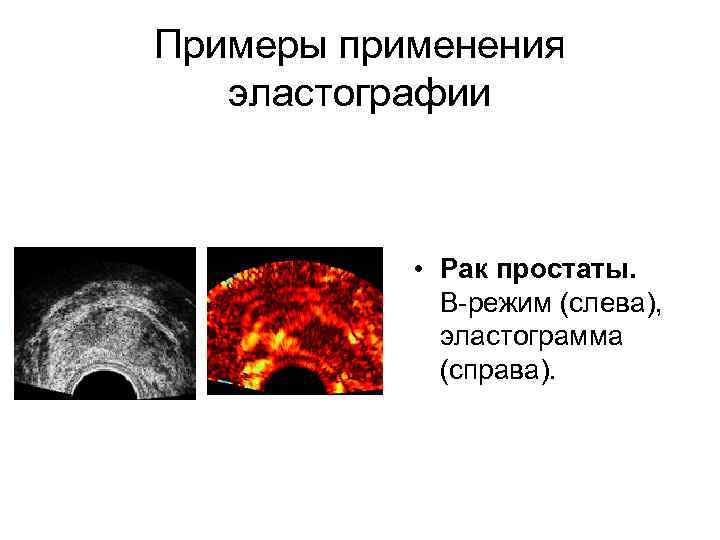

Примеры применения эластографии • Рак простаты. B-режим (слева), эластограмма (справа).

Примеры применения эластографии • Рак простаты. B-режим (слева), эластограмма (справа).